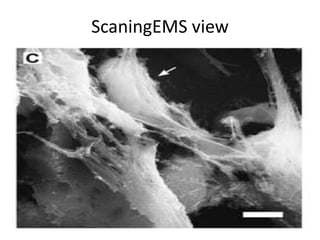

Neutrophil Extracellular Traps (Spiderman)

NET & BACTERIA

NET &Bacteria

ScaningEMS view

Bacteria in Spidernet SEMS view